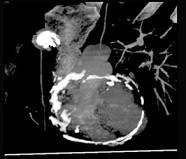

男性45岁,心悸气促乏力,下肢肿胀半年余,曾患肺结核,胸部CT扫描如图所示,请选择正确的选项为 ( )A、X线、CT为常用检查方法B、...

相关内容:男性,气促,下肢,半年,曾患,肺结核,胸部,扫描,如图,选项,常用,检查,方法